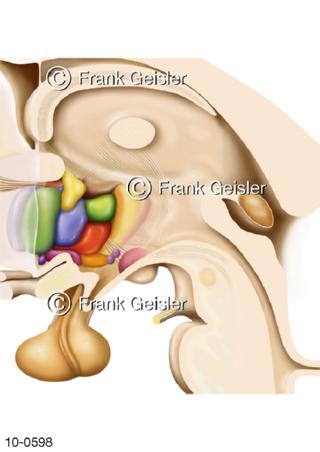

Bildergalerie Nervensystem

Bilder zum Nervensystem,dem Gehirn, Teil des zentralen Nervensystem, Zentralnervensystem ZNSmit Rückenmark, Abbildungen zum Nervengeflecht (Nervenplexus), die Verflechtungen von Nervenfasern, aus der Wirbelsäule hervortretende Nervenäst sowie Nervenzellen der Nerven